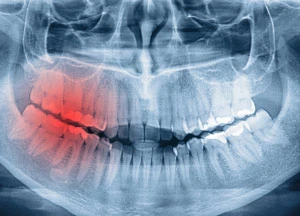

Dental injuries can be divided into two categories: direct injuries and indirect injuries. A direct injury can occur when the head or mouth is struck by or strikes an object. While indirect injuries happen when an open mouth is shut abruptly, causing the lower jaw’s teeth to be crushed into the upper teeth.

- Fractured Teeth- Dental professionals have four different classifications for fractured teeth, which are classified by the number of layers that are involved in the injury. Fractured teeth are treated similarly to avulsed teeth.